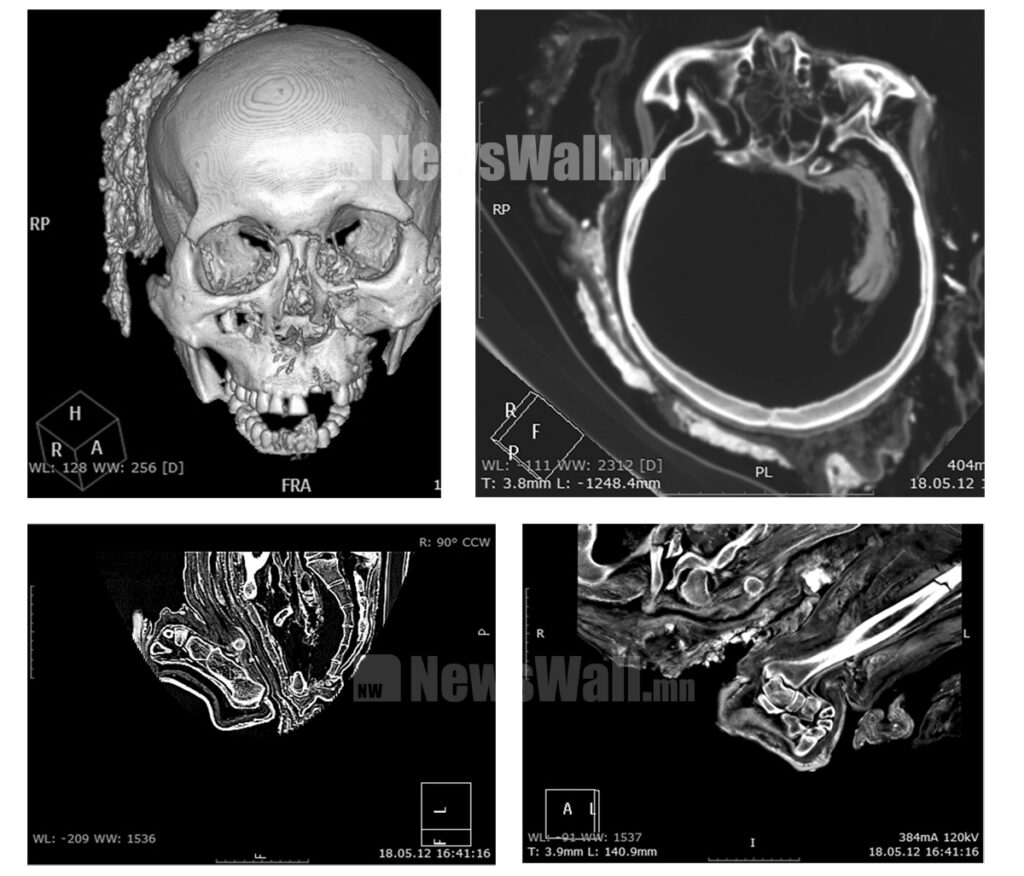

Мөн энэхүү олдворыг рентген аппаратанд оруулахад насны баримжаа 24-27 орчим гэж үзсэн бөгөөд дунд чөмөгт яс, тахилзуур ясны уртаар өндрийг баримжаалахад 170-172 см өндөртэй байсан. Ууц, ахар сүүлний хэлбэрээс харахад эрэгтэй хүн байх магадлал илүү өндөр хэмээн дүгнэсэн байна.